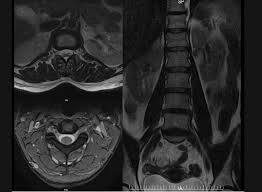

Estimate the cost of your mri or ct scan at american health imaging with our simple calculator. $800 pesos ($43.24 usd) mri of lumbar spine without dye: Super angebote für mri procedure hier im preisvergleich. Rotator cuff tears can often be diagnosed by physical examination, but cannot be confirmed without imaging. A mri in salt lake city costs $890 on average when you take the median of the 17 medical providers who perform mri procedures in salt lake city, ut. Average prices are for mri procedures performed at honorhealth facilities around the valley, and do not include physicians' fees. When i called one facility, they told me the mri i described would cost $1,600. In different conditions, the cost for even just one mri scan can surpass $13,000. They can range from $300 to $9000. Mri spine cervical w/o cont. I went to my gp after about 6 weeks of shoulder pain who said i'd torn something in my shoulder & referred me to physio, who i saw today. Please contact your physician's office and health insurance provider directly for price information. Our experienced staff are friendly and approachable, and can answer any.

When i called one facility, they told me the mri i described would cost $1,600. Your doctor or healthcare professional has recommended an mri scan because it is the best way to make an accurate diagnosis of your condition. For an mri of the spine, united pays the facility $1,005. $9,082 pesos ($490.91 usd) total actual cost (mexico): Mri spine cervical w/o cont.

Average prices are for mri procedures performed at honorhealth facilities around the valley, and do not include physicians' fees. I went to my gp after about 6 weeks of shoulder pain who said i'd torn something in my shoulder & referred me to physio, who i saw today. How much does an mri cost? What conditions does it treat? Super angebote für mri procedure hier im preisvergleich. On mdsave, the cost of a mri/ct with arthrogram ranges from $825 to $2,773. Please contact your physician's office and health insurance provider directly for price information. How much does a mri/ct with arthrogram cost? Rotator cuff tears can often be diagnosed by physical examination, but cannot be confirmed without imaging. How much does an mri cost? $9,082 pesos ($490.91 usd) total actual cost (mexico): These different factors contribute to the cost of the scan, but in general, an mri's cost can range from as low as $400 upwards to $3500. $800 pesos ($43.24 usd) mri of lumbar spine without dye: